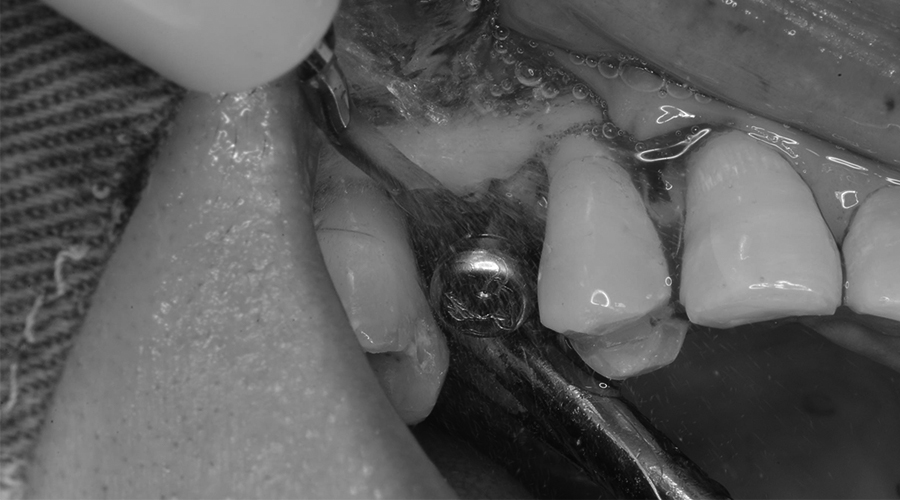

治療中

除去した

インプラント体